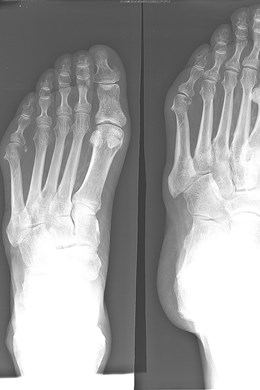

Die bunionette ontstaat meestal door een lichte scheefstand van het vijfde middenvoetsbeentje en overdruk van te smal schoeisel.

De belangrijkste behandeling bestaat uit goed schoeisel eventueel aangevuld met steunzolen. Bij ernstige pijnklachten of last kan een ingreep wenselijk zijn. Via een incisie van 2 à 3 mm brengen we een klein boortje in. We zagen hiermee een middenvoetsbeentje door, om de voet wat smaller te maken.

Op die manier verdwijnt de uitstekende pijnlijke knobbel.